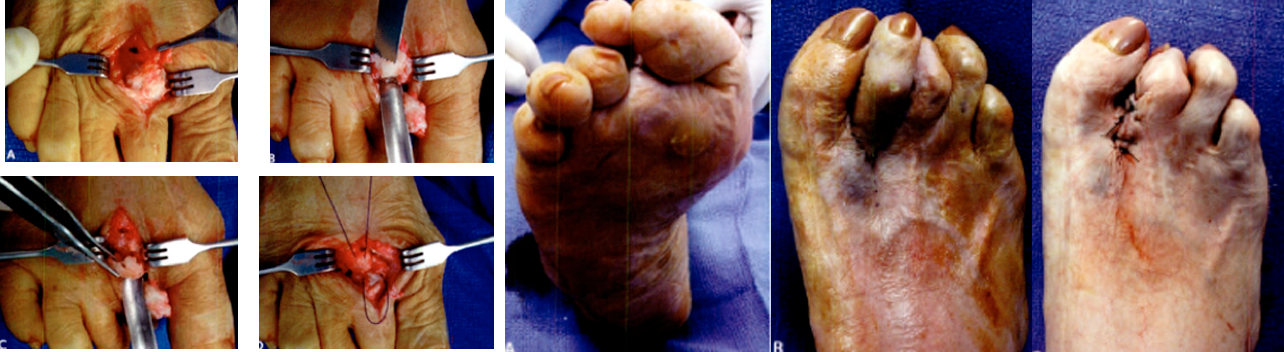

Principios de la Técnica

Corrección en el ápice o ángulo de la deformidad

Fijación Dinámica Blanda

- Fracturas Múltiples

- Osteotomías

- Liberación de Partes Blandas (Contractura)

- Tenotomías y Capsulotomías

- Realineación Anatómica

- Vendaje Blando, protege las heridas, alineación del pie, estabilidad relativa de las osteotomías

- Marcha con carga total inPieDiabeticota

Dedo Supraducto - Metatarsalgia

Pre y Post op

Dr. Luis Villanueva

Dedo Supraducto - Metatarsalgia

Dr Meyerson (USA)

Pre y Post op